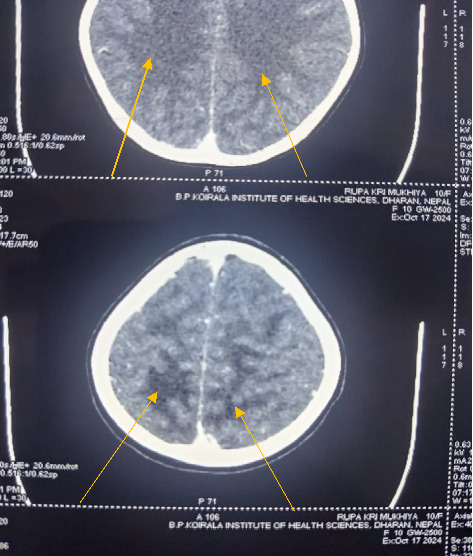

Posterior reversible encephalopathy syndrome (PRES) is a condition that manifests with symptoms like altered mental status, seizures, vision impairment, and vasogenic edema primarily affecting the occipital and parietal lobes, with occasional involvement of the frontoparietal regions. We report a case of a 10 year old girl who arrived at the pediatric emergency department with generalized swelling, dark-colored urine, and two days of seizures following recent throat infection. Her blood pressure consistently exceeded the 95th percentile by +12 mm Hg, indicating stage 2 hypertension. A computed tomography (CT) scan showed hypodensities (edema) in the parieto-occipital white matter, consistent with PRES. Due to limited resources, magnetic resonance imaging (MRI) could not be performed. The patient was treated symptomatically with levetiracetam for seizures and furosemide and amlodipine for hypertension. By the fifth day of hospitalization, the patient experienced significant improvement, with a return to normal appetite, urine color, and neurological function. Early diagnosis contributed to her full recovery. Physicians in resource limited settings should have high degree of suspicion of pediatric PRES and perform detailed history taking, examination, laboratory investigations and imaging (whenever available) for management of pediatric PRES.